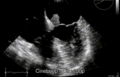

Echocardiogram of atrial myxoma -

Echocardiogram showing atrial myxoma[9]